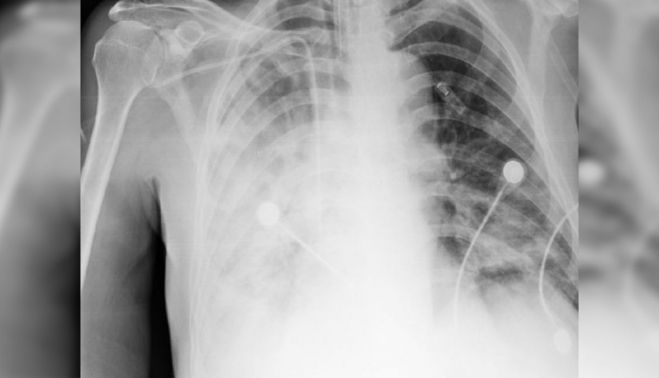

La melioidosis suele afectar a los pulmones en la versión aguda de la enfermedad, aunque también otros órganos pueden sufrir complicaciones.

Las manifestaciones clínicas pueden ir desde neumonía o bronquitis a abscesos benignos o una septicemia con consecuencias fatales.